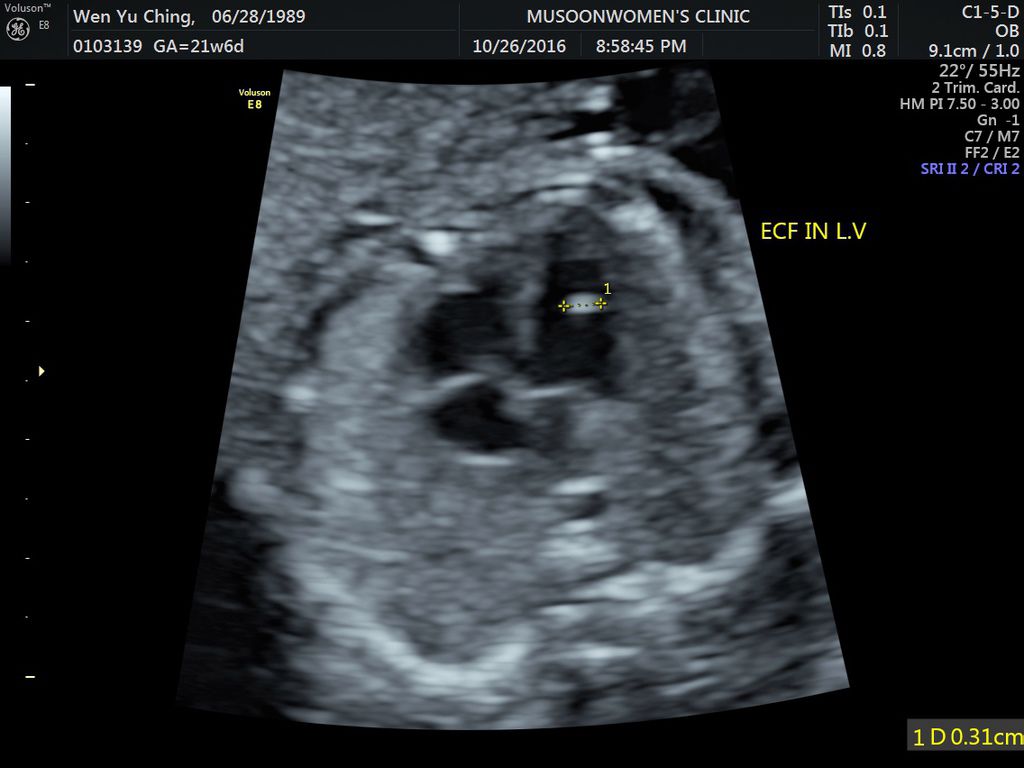

懷孕 (21-24W)高層次超音波: 左心室有一 顆小白點 嘖嘖